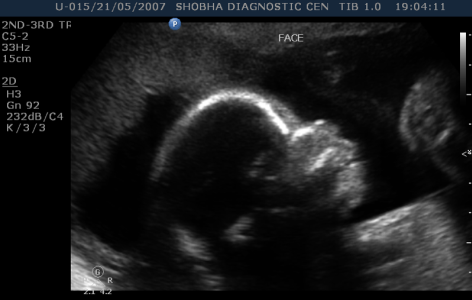

TARGETED OR ANOMALY SCAN (18-22 WEEKS)

- Thorough scanning of your baby is done to know if baby is developing normally or not. Special attention is paid to brain, face, spine, heart, stomach, bowel, kidneys & limbs.